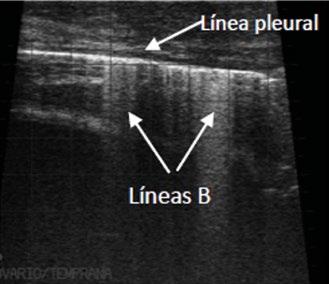

Patrón aireado: un pulmón aireado no puede visualizarse por ecografía, generándose una imagen artefactual en forma de líneas horizontales, paralelas e hiperecogénicas (líneas A).

Puntuación 2

Patrón intersticial: líneas verticales que llegan al final de la pantalla, hiperecogénicas. Se mueven sincrónicamente con el desplazamiento pleural (líneas B).

Figura 1. Score de lesión pulmonar (Adams y Buczinski, 2016).